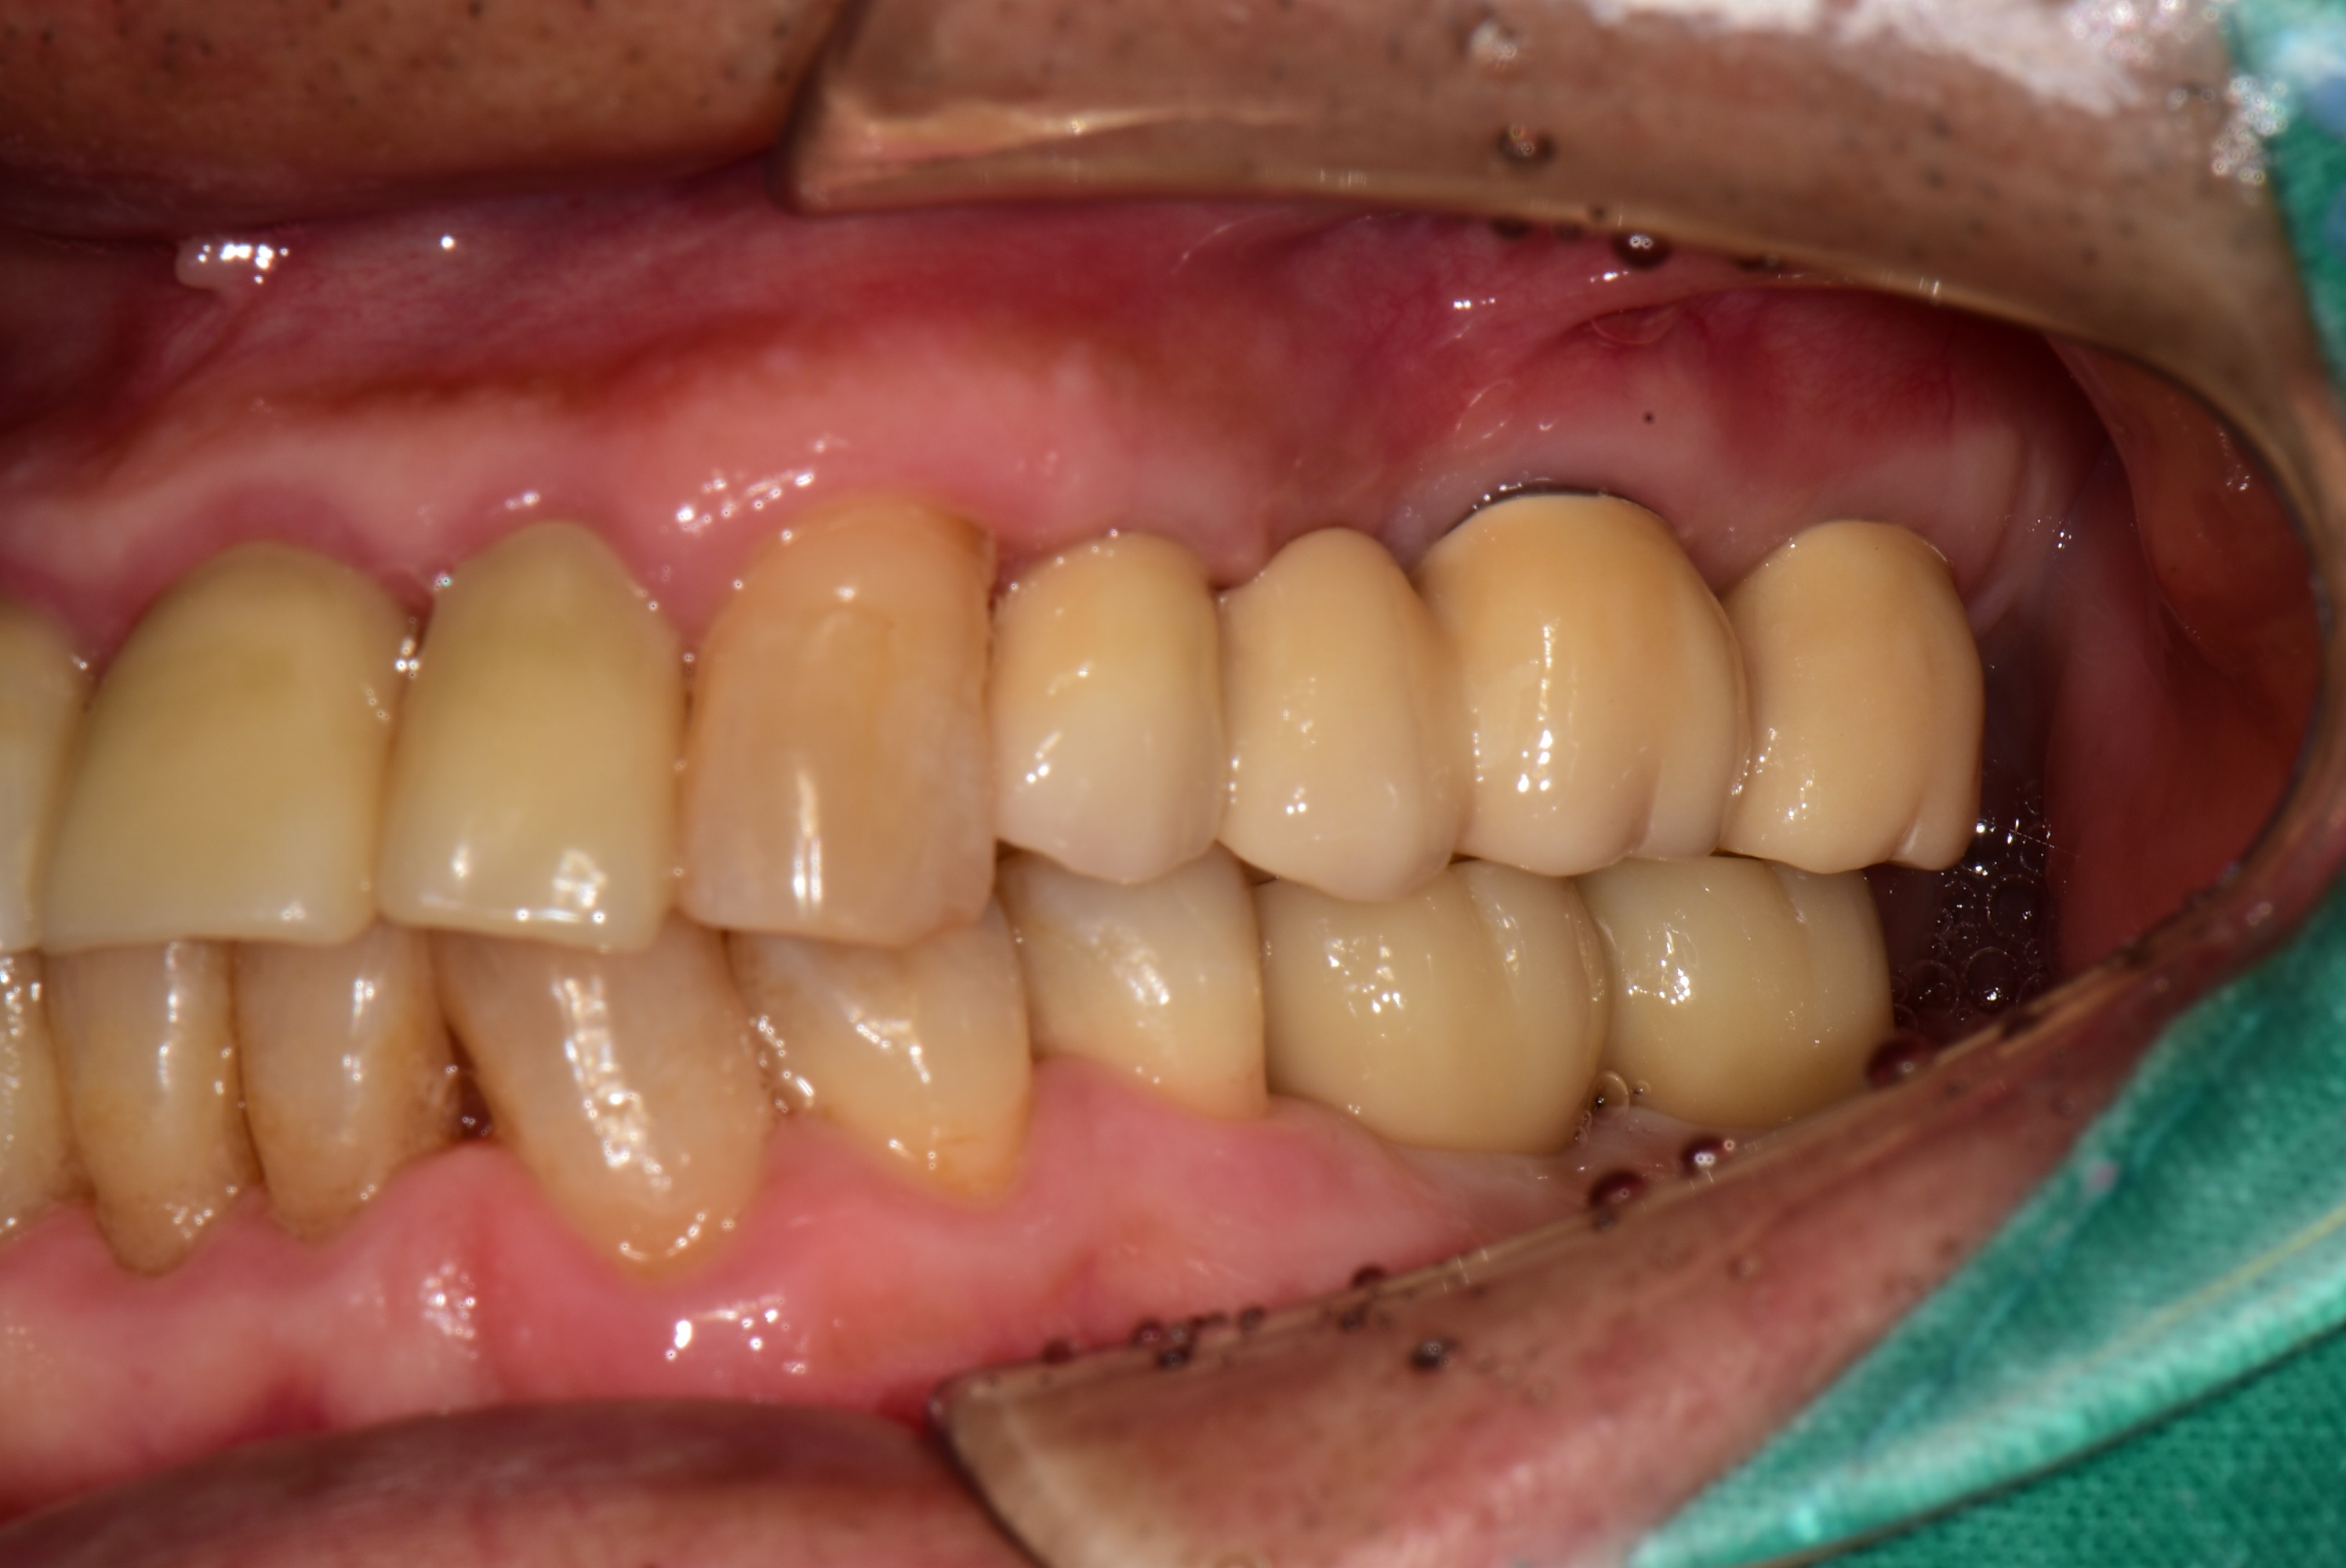

어금니 부위 10개 임플란트, 앞니 2개 임플란트를 식립하여 전체 치아를 재건해드린 사례입니다.

<임플란트 치료 후>